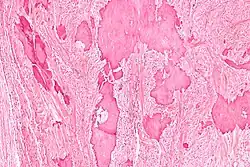

Low magnification micrograph of a calcified ovarian fibroma in the context of nevoid basal cell carcinoma syndrome. H&E stain.

On gross pathology, they are firm and white or tan. On microscopic examination, there are intersecting bundles of spindle cells producing collagen.

There may be thecomatous areas (fibrothecoma). The presence of an ovarian fibroma can cause ovarian torsion in some cases.

Diagnosis is usually made by ultrasonography showing a solid ovarian lesion, or, on some occasions, mixed tumors with solid and cystic components.[1] Computed tomography and magnetic resonance imaging can also be used to diagnose fibromas. In a series of 16 patients, 5 (28%) showed elevated levels of CA-125.[1] Histopathology demonstrates spindle-shaped fibroblastic cells and abundant collagen.[3]